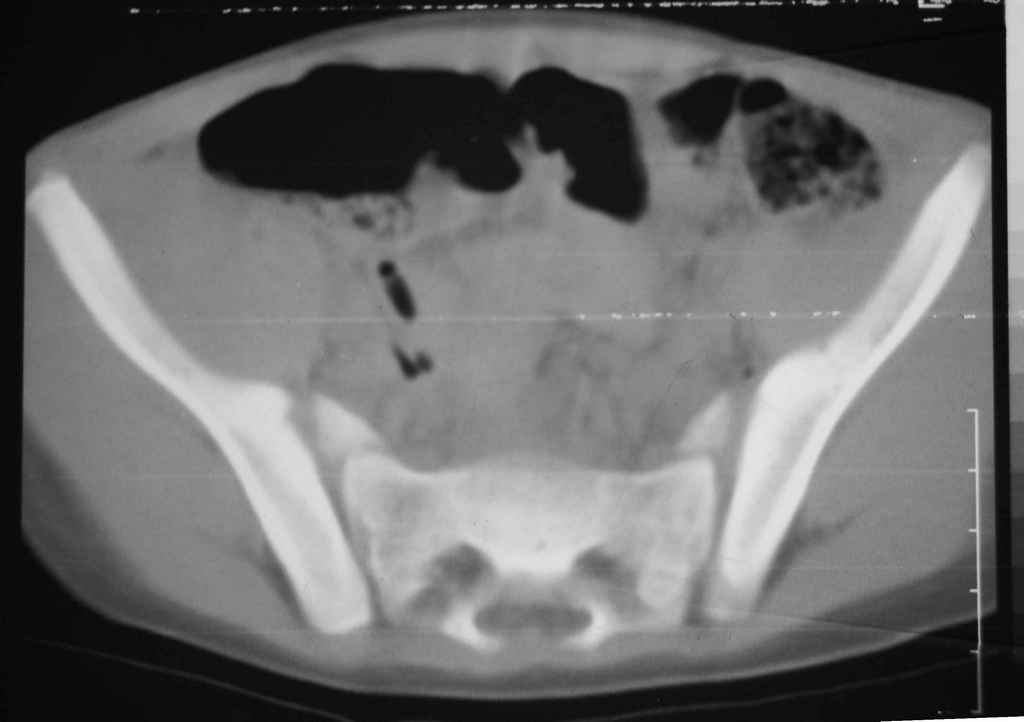

Уважаемые коллеги, помогите определиться с тактикой лечения. Ребёнок 7 лет, травма 11.09.08, поступил с травматическим вывихом бедренной кости.

Вывих вправлен, конечность фиксирована на скелетном вытяжении. Что делать с переломом подвздошной кости? Лечить консерватино или оперировать?